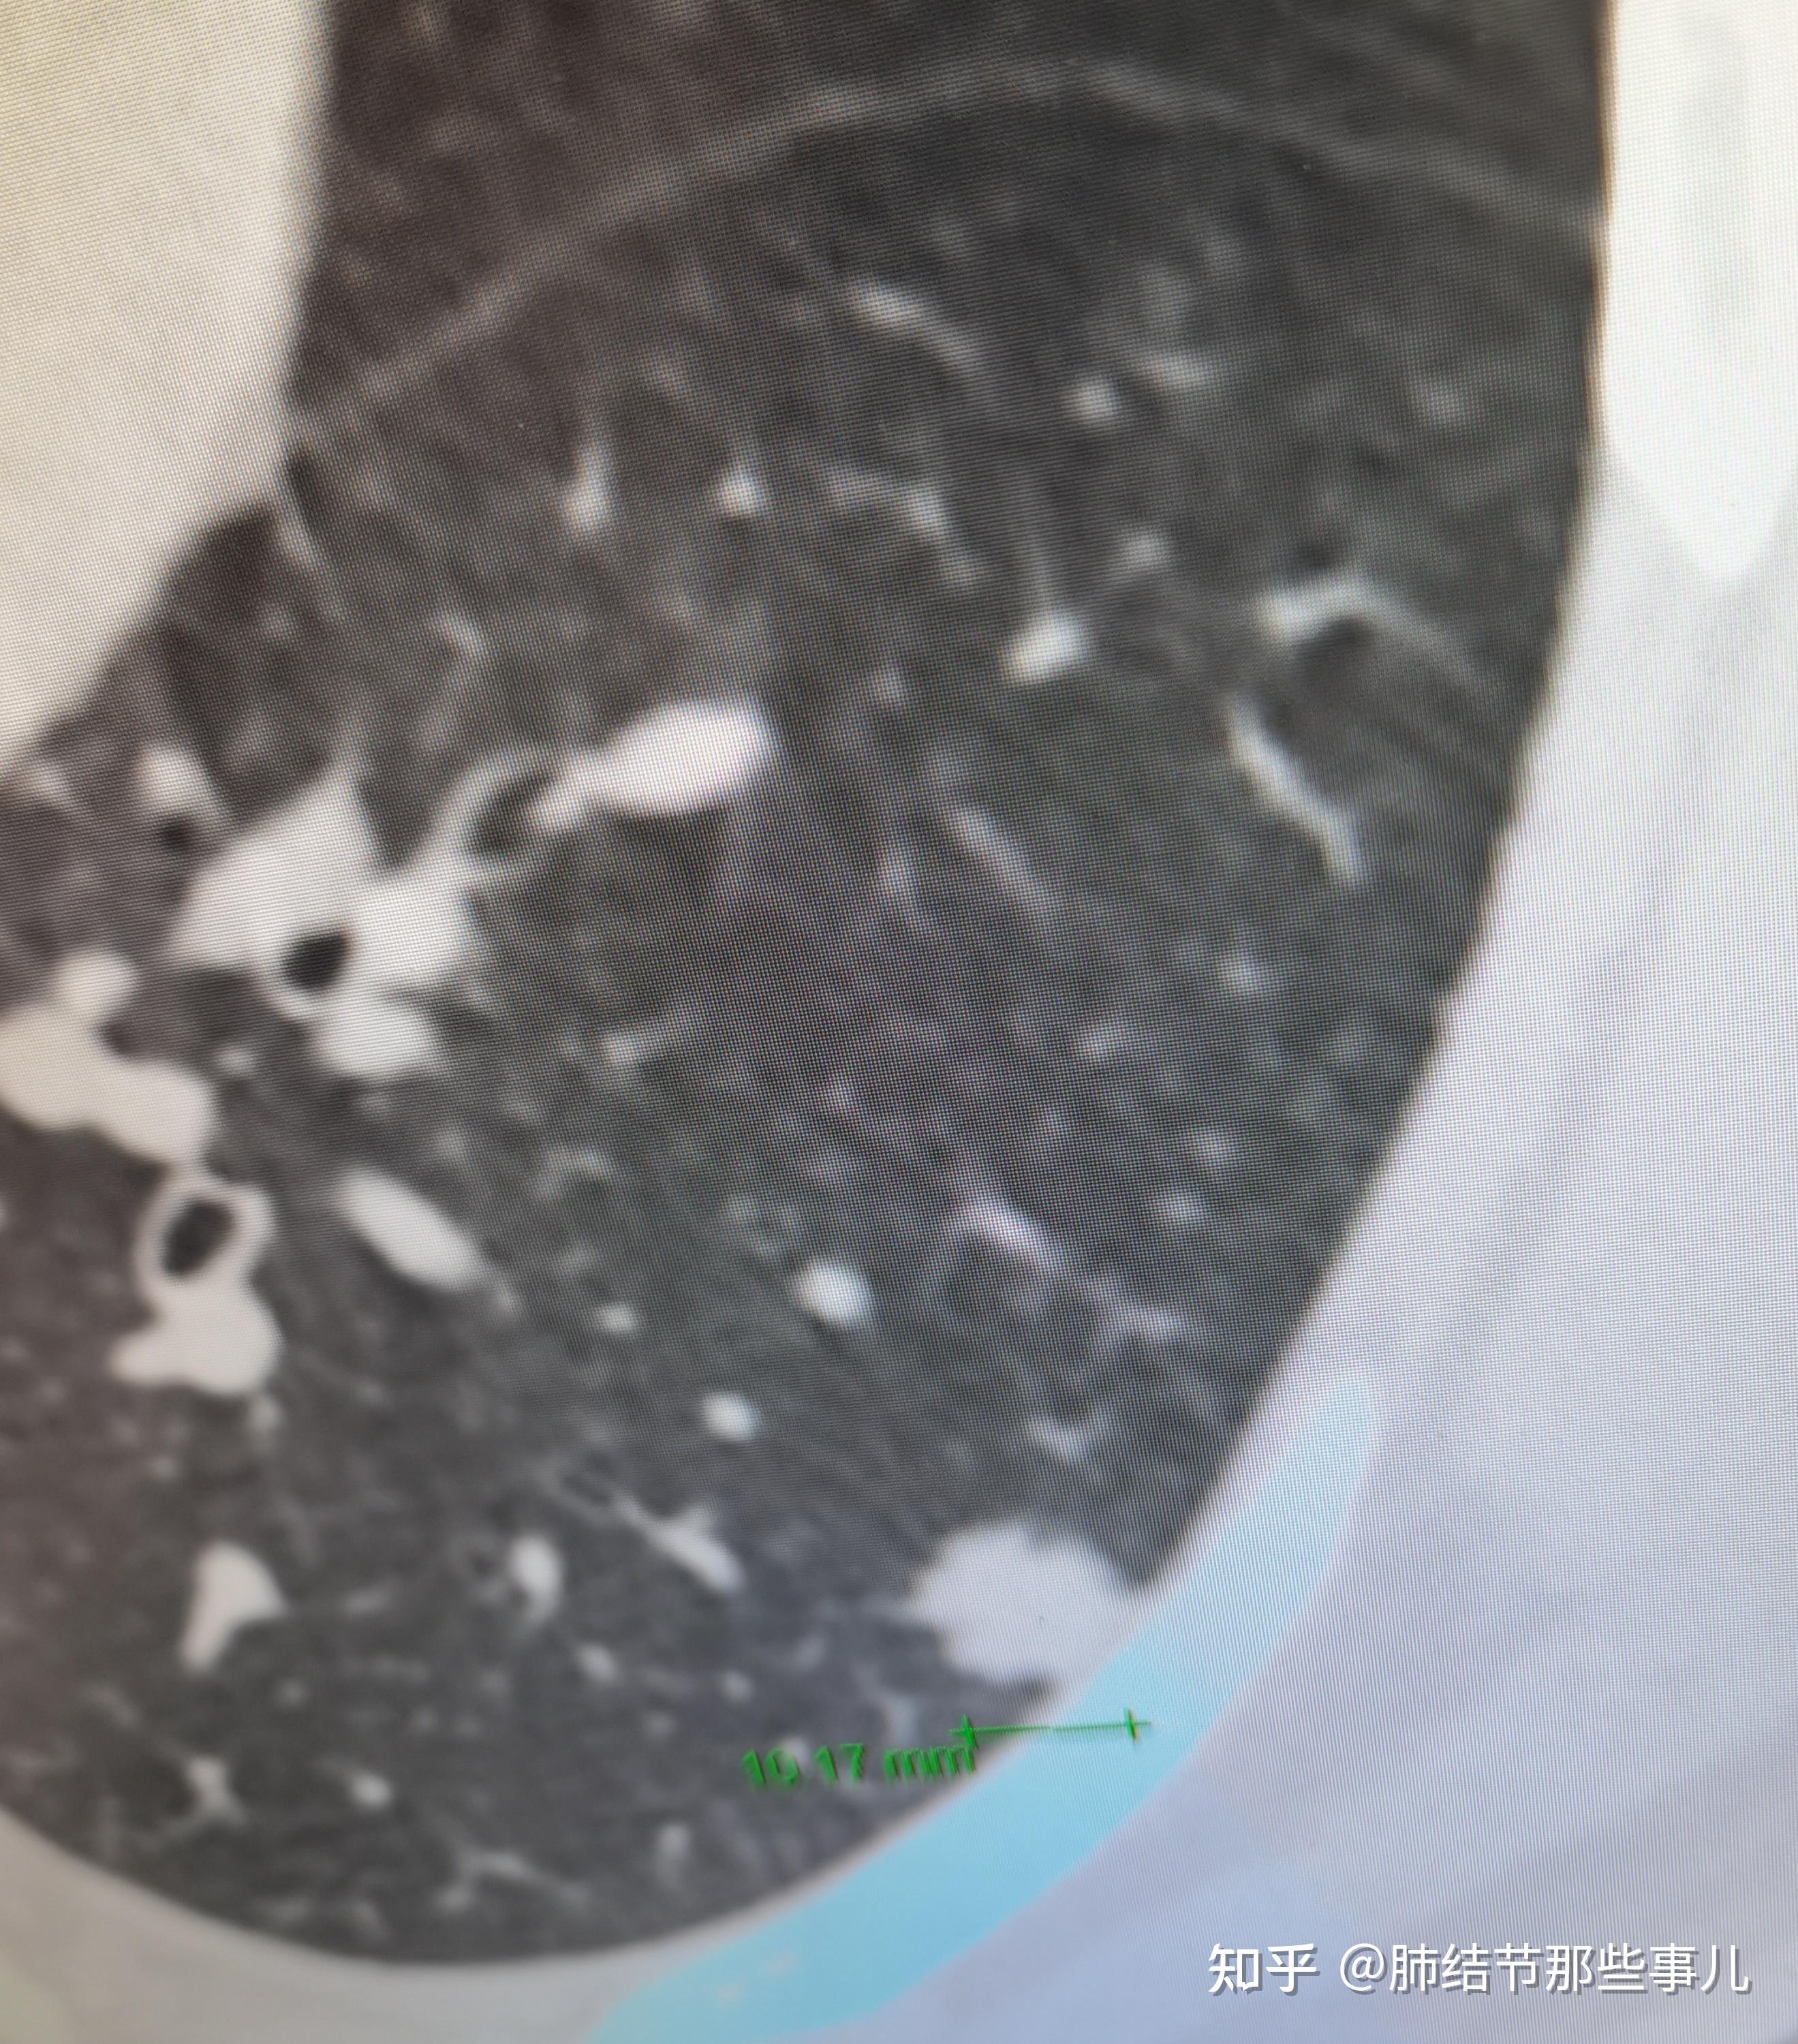

恶之花黏液腺癌一例30岁年青男性的10mm肺实性结节